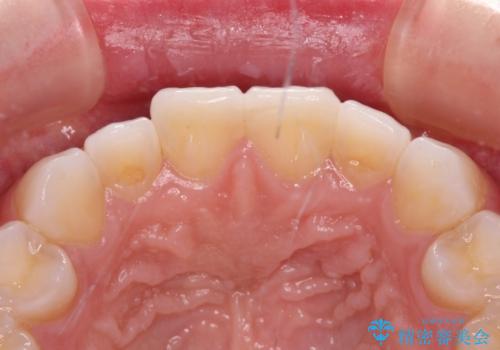

- 矯正治療で歯列を整えた後、前歯の形が気になった患者様です。

矯正前の歯列の影響で、前歯の先端が非対称にすり減ってしまったため、矯正治療後の形が非対称になっていました。

むし歯はなく、矯正治療で咬み合わせが改善していたので、侵襲量の少ないラミネートベニアにて治療することとしました。

ラミネートベニアは切削量が少ないことがメリットとしてあげられますが、色調を周辺と合わせられないこと、接着境界線が長く汚れや歯石が溜まりやすいことがデメリットとして考えられます。

また、接着境界線にむし歯がある場合には適用外となるなど、適用症例を選ぶため、治療に際して担当医としっかりと相談することが大切です。